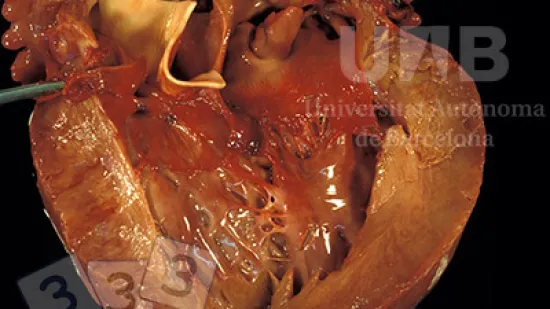

心脏观察到的病变是

周 09-3月-2016